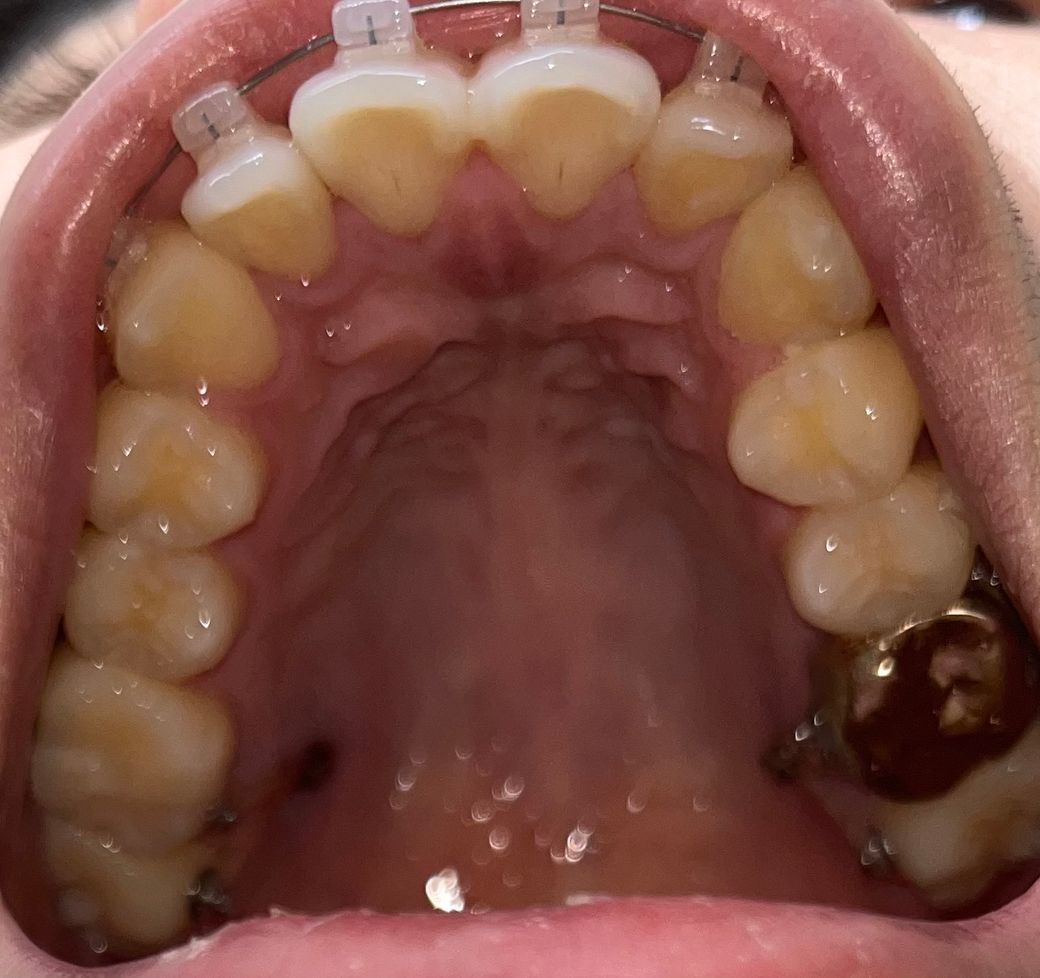

악궁이 좁은 편인가요 ?

안녕하세요. 갑자기 제 악궁크기가 적당한건지 궁금증이 들었고, 월치료때 물어보자니 좀 오래남아서 여기다가 글 올립니다. 사진보고 답변남겨주세요!

악궁을 형성하는 아치 형태가 조금 좁아 보입니다.

아치가 넓게 퍼진 경우와 좁고 긴 경우가 있는데 좁고 긴것으로 보입니다.

일반 사람들에 비해 악궁이 좁은 편은 맞습니다. 하지만 정확한 악궁 크기를 판단하기 위해서는 아래턱 및 위턱의 구조 등을 평가해야 합니다. 즉 악궁의 크기는 골격적인 부분이므로 아래와 위턱이 서로 조화를 이룬다면 악궁이 좁은 것 자체는 문제가 되지 않습니다. 또한 과거와 달리 RPE 장치를 통해서 상악이 과도하게 좁은 경우에는 확장을 할 수 있습니다.

사진만 봐서 판단한다면 악궁폭이 좁은것으로 판단됩니다.

사진으로 보기에 악궁이 조금 좁아보인듯 합니다.